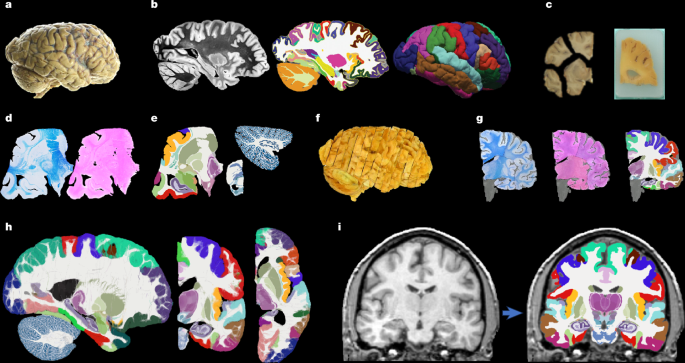

Hemispheres from five individuals (including half of the cerebrum, cerebellum and brainstem), were used in this study, following informed consent to use the tissue for research and the ethical approval for research by the National Research Ethics Service Committee London – Central. All hemispheres were fixed in 10% neutral buffered formalin (Fig. 1a). The laterality and demographics are summarized in Supplementary Table 1; the donors were neurologically normal, but one case had an undiagnosed, asymptomatic tumour (diameter roughly 10 mm) in the white matter, adjacent to the pars opercularis. This tumour did not pose issues in any of the processing steps described below.

After MRI scanning, each hemisphere is dissected to fit into standard 74 mm × 52 mm cassettes. First, each hemisphere was split into cerebrum, cerebellum and brainstem. Using a metal frame as a guide, these were subsequently cut into 10-mm-thick slices in coronal, sagittal and axial orientation, respectively. These slices were photographed inside a rectangular frame of known dimensions for pixel size and perspective correction; we refer to these images as ‘whole slice photographs’. Although the brainstem and cerebellum slices all fit into the cassettes, the cerebrum slices were further cut into as many blocks as needed. ‘Blocked slice photographs’ were also taken for these blocks (Fig. 1c, left).

After standard tissue processing steps, each tissue block was embedded in paraffin wax and sectioned with a sledge microtome at 25-μm thickness. Before each cut, a photograph was taken with a 24 MPx Nikon D5100 camera (ISO = 100, aperture = f/20, shutter speed = automatic) mounted right above the microtome, pointed perpendicularly to the sectioning plane. These photographs (henceforth ‘blockface photographs’) were corrected for pixel size and perspective using fiducial markers. The blockface photographs have poor contrast between grey and white matter (Fig. 1c, right) but also negligible nonlinear geometric distortion, so they can be readily stacked into 3D volumes. A two-dimensional convolutional neural network (CNN) pretrained on the ImageNet dataset60 and fine-tuned on 50 manually labelled examples was used to automatically produce binary tissue masks for the blockface images.

We mounted on glass slides and stained two consecutive sections every N (see below), one with H&E and one with LFB (Fig. 1d). The sampling interval was N = 10 (that is, 250 μm) for blocks that included subcortical structures in the cerebrum, medial structures of the cerebellum or brainstem structures. The interval was N = 20 (500 μm) for all other blocks. All stained sections were digitized with a flatbed scanner at 6,400 DPI resolution (pixel size 3.97 μm). Tissue masks were generated using a two-dimensional CNN similar to the one used for blockface photographs (pretrained on ImageNet and fine-tuned on 100 manually labelled examples).

Dense labelling of histology

Segmentations of 333 ROIs (34 cortical, 299 subcortical) were made by authors E.R., J.A. and E.B. (with guidance from D.K., M.B., Z.J. and J.C.A.) for all the LFB sections, using a combination of manual and automated techniques (Fig. 1e). The general procedure to label each block was (1) produce an accurate segmentation for one of every four sections, (2) run SmartInterpol28 to automatically segment the sections in between and (3) manually correct these automatically segmented sections when needed. SmartInterpol is a dedicated artificial intelligence technique that we have developed specifically to speed up segmentation of histological stacks in this project.

To roughly initialize the 3D reconstruction, we relied on the stacks of blockface photographs. Specifically, we used our previously presented hierarchical joint registration framework23 that seeks to (1) align each block to the MRI with a similarity transform, by maximizing the normalized cross-correlation of their intensities while (2) discouraging overlap between blocks or gaps in between, by means of a differentiable regularizer. The similarity transforms allowed for rigid deformation (rotation, translation), as well as isotropic scaling to model the shrinking due to tissue processing. The registration algorithm was initialized with transforms derived from the whole slice, blocked slice and blockface photographs (see details in ref. 26). The registration was hierarchical in the sense that groups of transforms were forced to share the same parameters in the earlier iterations of the optimization, to reflect our knowledge of the cutting procedure. In the first iterations, we clustered the blocks into three groups: cerebrum, cerebellum and brainstem. In the following iterations, we clustered the cerebral blocks that were cut from the same slice and allowed translations in all directions, in-plane rotation and global scaling. In the final iterations, each block alignment was optimized independently. The numerical optimization used the LBFGS algorithm63. The approximate average error after this procedure was about 2 mm (ref. 23). A sample 3D reconstruction is shown in Fig. 1f.

Running SbR for each stain and section independently (that is, LFB to resampled MRI and H&E to resampled MRI) yields a reconstruction that is jagged and sensitive to folds and tears. One alternative is to register each histological section to each neighbour directly, which achieves smooth reconstructions but incurs the so-called ‘banana effect’: that is, a straightening of curved structures14. We have proposed a Bayesian method that yields smooth reconstructions without the banana effect25. This method follows an overconstrained strategy by computing registrations between LFB and MRI, H&E and MRI, H&E and LFB, each LFB section and the two nearest neighbours in either direction across the stack, each H&E section and its neighbours, and each MRI slice and its neighbours. For a stack with S sections, this procedure yields 15xS-18 registrations, whereas the underlying dimensionality of the spanning tree connecting all the images is just 3xS-1. We use a probabilistic model of SVFs to infer the most likely spanning tree given the computed registrations, which are seen as noisy measurements of combinations of transforms in the spanning tree. The probabilistic model uses a Laplace distribution, which relies on L1 norms and is thus robust to outliers. Moreover, the properties of SVFs enable us to write the optimization problem as a linear program, which we solve with a standard simplex algorithm71. The result of this procedure was a 3D reconstruction that is accurate (it is informed by many registrations), robust and smooth (Figs. 1g and 2).

Every iteration of the atlas construction process comprises two steps. First, the current estimate of the atlas and the segmentations are coregistered one at a time using (1) a diffeomorphic deformation model based on SVFs parameterized by grids of control points and B-splines (as implemented in NiftyReg72), which preserves the topology of the segmentations; (2) a data term, which is the log-likelihood of the label at each voxel according to the probabilities given by the deformed atlas (with a weak Dirichlet prior to prevent logs of zero); and (3) a regularizer based on the bending energy of the field, which encourages regularity in the deformations. The second step of each iteration updates the atlas by averaging the segmentations. The procedure converged (negligible change in the atlas) after five iterations. Slices of the atlas are shown in Figs. 1h and 3.

Sample segmentations with this method can be found in Fig. 1h (in vivo) and Fig. 4 (ex vivo).

We used a simplified version of the NextBrain atlas when segmenting the 100-μm scan, to better match the ROIs of the automated segmentation and the ground truth (especially in the brainstem). This version was created by replacing the brainstem labels in the histological 3D reconstruction (Fig. 1g, right) by new segmentations made directly in the underlying MRI scan. These segmentations were made with the same methods as for the 100-μm isotropic scan. The new combined segmentations were used to rebuild the atlas.